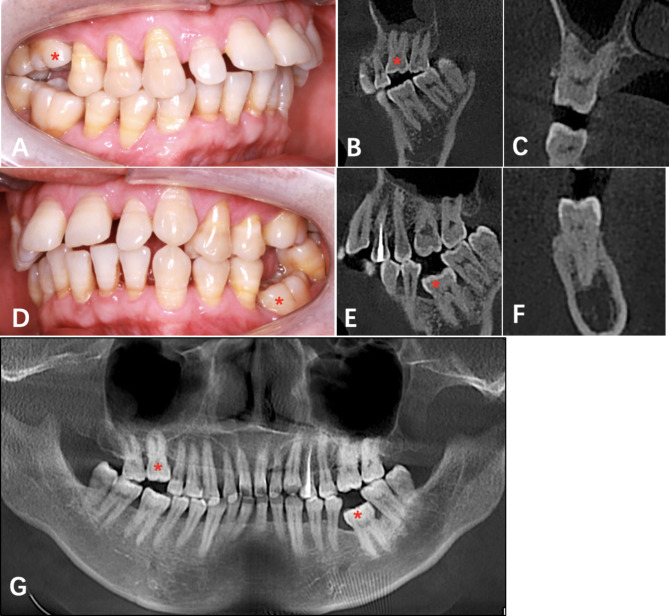

The proband’s father also had two impacted teeth in the dentition. The #16 and #36 were below the occlusion plane leading to a 3 mm open-bite on the right and a 6 mm open-bite on the left (Fig. 8A). Alveolar bone resorption indicates chronic periodontitis in this patient. Radiographic information showed that the morphology of #16 and #36 was normal, the roots were well developed, and there were no abnormalities in periapical tissue (Fig. 8B-G).

Fig. 8.

Clinical and radiographic information of the proband’ father. (A, intraoral right view. B, the sagittal image of 16. C, the coronal image of 16. D, intraoral left view. E, the sagittal image of #36. F, the coronal image of #36. G, panoramic radiograph. “*” represent the PFE involved tooth.)